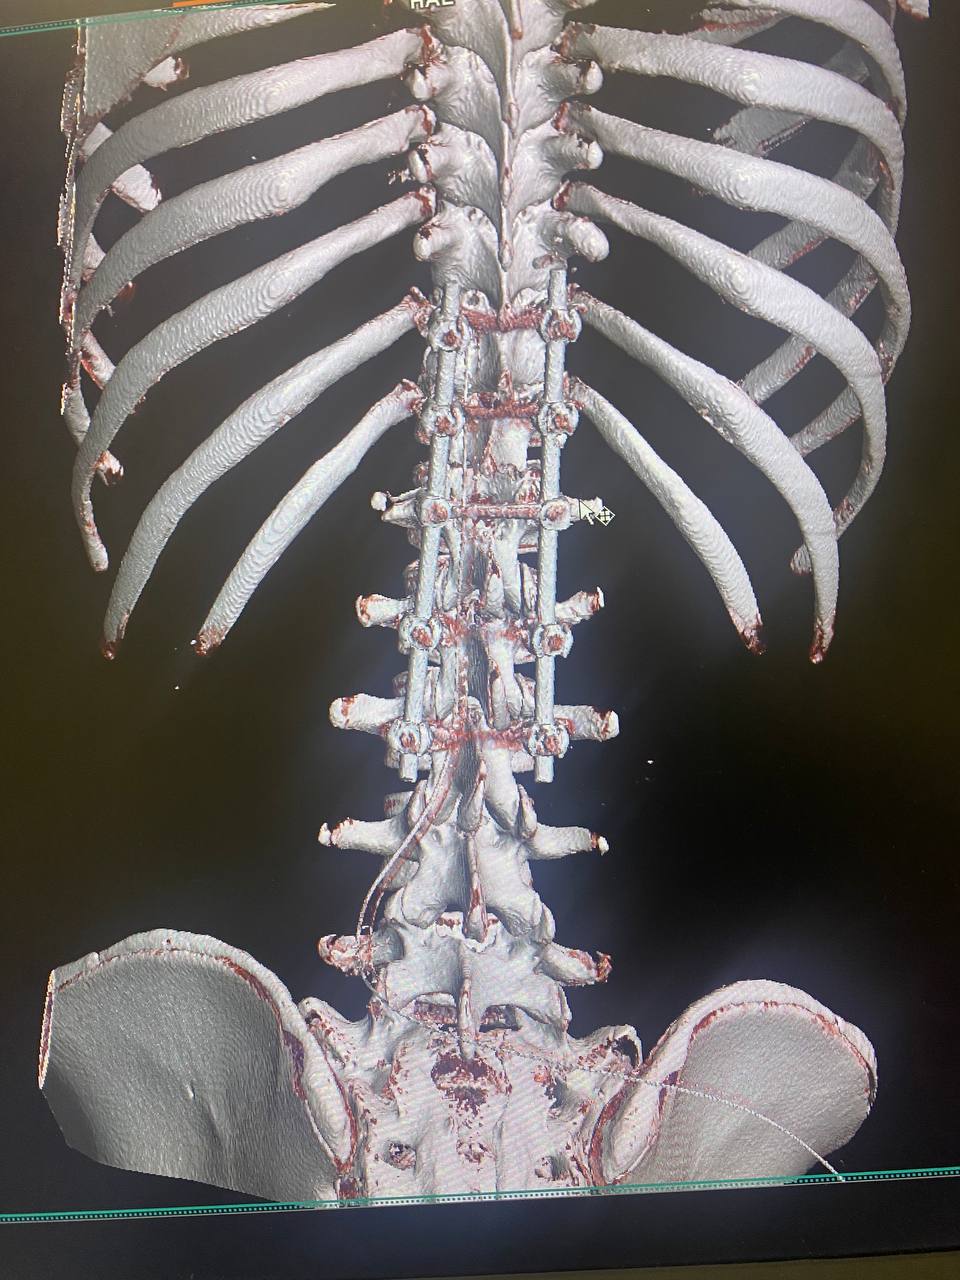

Медики успішно виконали складне нейрохірургічне втручання — транспедикулярну стабілізацію хребта. Такі поранення є надзвичайно небезпечними, оскільки нестабільність хребта може призвести до ураження спинного мозку та незворотних наслідків.

Під час високоточної операції нейрохірурги встановили транспедикулярні гвинти та фіксуючу систему, що дозволило стабілізувати ушкоджений сегмент хребта, відновити його анатомічне положення та створити умови для подальшого зрощення й реабілітації.